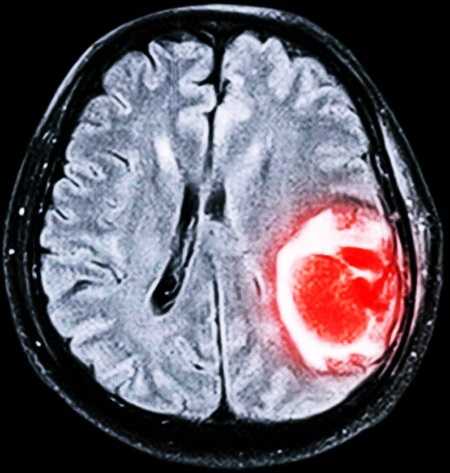

Отёчность при инсульте

Следствием ишемического либо геморрагического инсульта становится мозговое набухание. Нарушенное кровообращение при ишемической форме сопровождается закупоркой сосуда, что приводит к недостатку кислорода, некрозу тканей мозга. При геморрагическом виде кровоизлияние локализуется под мозговой оболочкой. Это приводит к резкому увеличению показателей внутричерепного давления и отёчности.

Изначально набухание связано с нарушением метаболизма в месте поражения и располагается в веществе мозга. По прошествии 6 часов развивается вазогенный тип отёчности, который локализуется в белом веществе. Подобное явление происходит вследствие проникновения ликвора и сосудистых белков во внеклеточное пространство. Ткани начинают отмирать, провоцируя скопление жидкости в капиллярах.

Отёк мозга при инсульте появляется стремительно, он локализуется в любой части мозгового вещества. От родственников пострадавшего требуется вовремя заметить нездоровые проявления и немедленно обратиться за медицинской помощью.